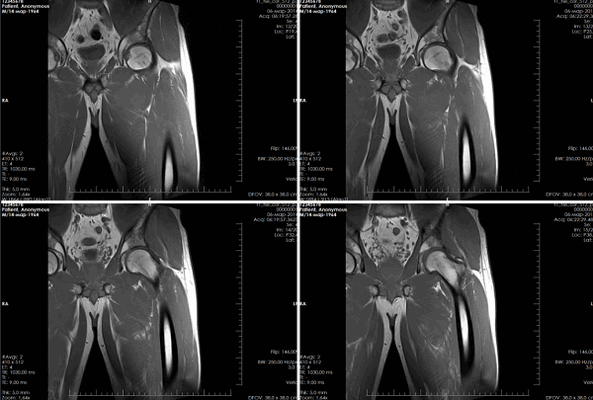

(Слева) МР-артрография, PDBИ, режим подавления сигнала от жира, косой аксиальный срез: определяется смещенный костно-хрящевой осколок с уплощением головки бедренной кости и сопутствующим отеком костного мозга, что указывает на травматический коано-хрящевой перелом головки бедренной кости.

(Справа) КТ после вывиха тазобедренного суаава, сагиттальный срез: определяется небольшая коано-хрящевая вколоченная травма № передней поверхности головки бедренной кости. Утрата хряща может быть заподозрена на основании неровности кортикального слоя. Задний осколок откололся от вертлужной впадины.